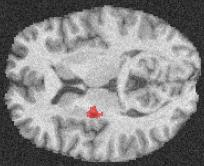

Machine learning models are typically deployed in a test setting that differs from the training setting, potentially leading to decreased model performance because of domain shift. If we could estimate the performance that a pre-trained model would achieve on data from a specific deployment setting, for example a certain clinic, we could judge whether the model could safely be deployed or if its performance degrades unacceptably on the specific data. Existing approaches estimate this based on the confidence of predictions made on unlabeled test data from the deployment's domain. We find existing methods struggle with data that present class imbalance, because the methods used to calibrate confidence do not account for bias induced by class imbalance, consequently failing to estimate class-wise accuracy. Here, we introduce class-wise calibration within the framework of performance estimation for imbalanced datasets. Specifically, we derive class-specific modifications of state-of-the-art confidence-based model evaluation methods including temperature scaling (TS), difference of confidences (DoC), and average thresholded confidence (ATC). We also extend the methods to estimate Dice similarity coefficient (DSC) in image segmentation. We conduct experiments on four tasks and find the proposed modifications consistently improve the estimation accuracy for imbalanced datasets. Our methods improve accuracy estimation by 18\% in classification under natural domain shifts, and double the estimation accuracy on segmentation tasks, when compared with prior methods.